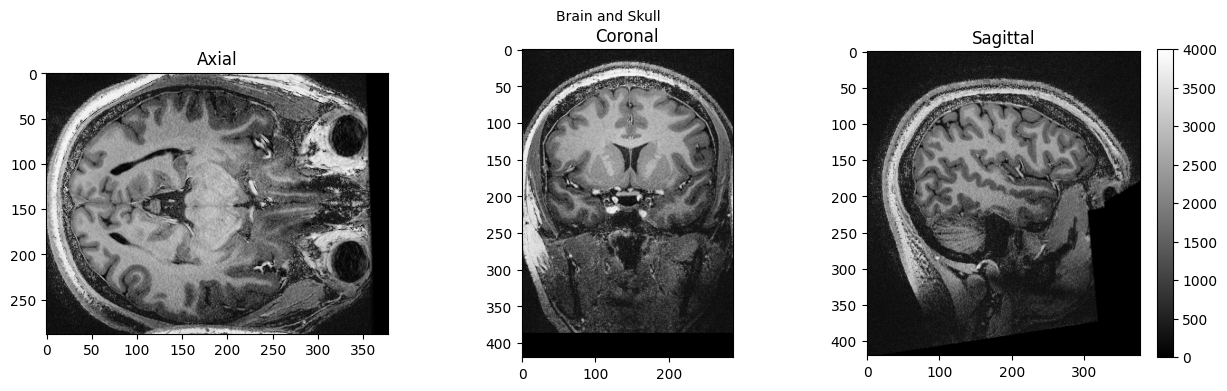

brain_full = nib.load('./sub-01_ses-01_7T_T1w_defaced.nii').get_fdata()

view_slices_3d(brain_full, slice_nbr=230, vmin=0, vmax=4000, title='Brain and Skull')